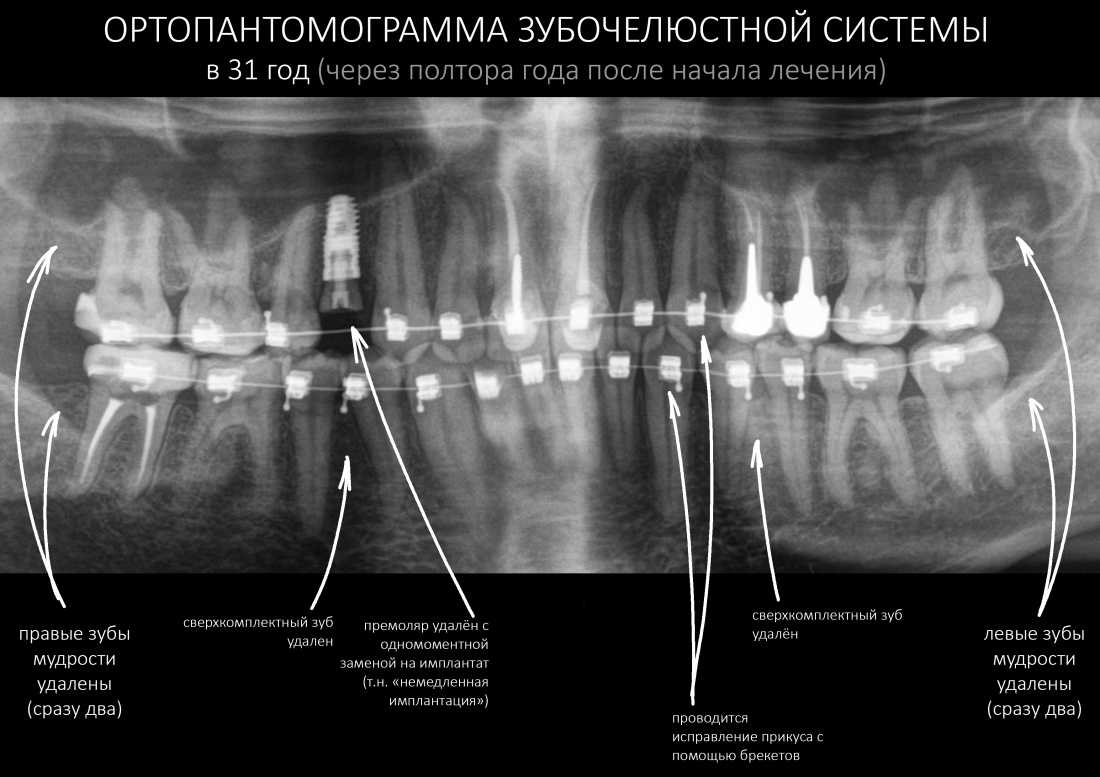

Условие 1. Предполагаемый план протезирования.

Не устаю повторять, что схема и тактика имплантации определяются, в первую очередь, планом протезирования, который составляет стоматолог-ортопед. Во всех отношениях он является главным, именно он определяет положение и количество имплантатов, необходимых для опоры предполагаемой протетической конструкции. Консультация стоматолога-ортопеда первична при планировании имплантологического лечения, и без неё лучше вообще не приступать к установке имплантатов.

Стоматолог-ортопед составляет план протезирования, который материализуется в хирургическом шаблоне:

Правильное положение имплантатов в адекватных объемах окружающих тканей — это залог успешного и долговечного протезирования. В связи с этим, категорически важно получить от ортопеда схему протезирования (и имплантации) еще до начала лечения. Проанализировав её, нужно определиться с возможностью стабилизировать имплантаты в правильном положении в существующих объемах костной ткани.